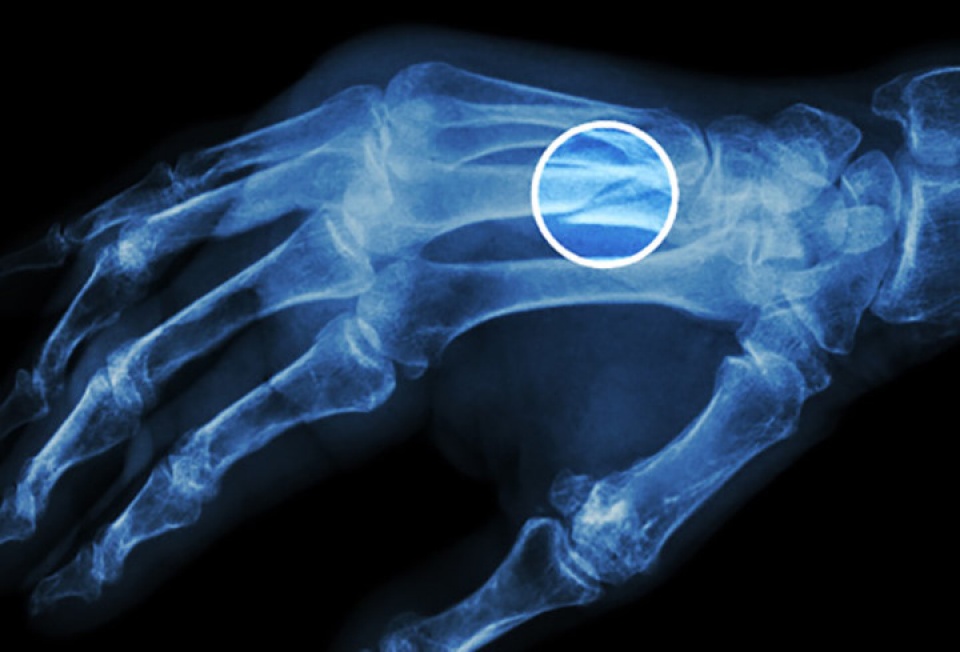

Gãy xương: Điều này có thể xảy ra ở mọi lứa tuổi, nhưng xương có thể giòn hơn ở người cao tuổi và dễ gãy. Ngoài ra chứng loãng xương đặc biệt phổ biến ở phụ nữ lớn tuổi. Canxi và vitamin D có thể giúp làm chậm lại hoặc ngăn chặn chứng loãng xương. (Nguồn: Webmd)